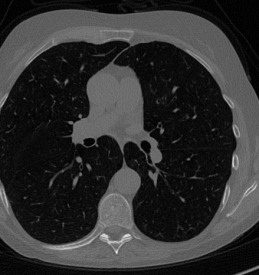

Here we present the results of RISING applied to the Mayo data set introduced in paragraph 4.1. As previously mentioned, we consider two sparse-view CT geometries, namely and . In Figure 4 we report the results for the protocol, achieved on one image of our test set. The top-left image represents the reconstruction. Even if only a small number of iterations are performed, the main structures of the abdomen are visible; however, the image is still blurry. In the image, shown in the upper-right corner, we notice that the TV regularizer has acted to totally eliminate the artifacts and noise, improving the uniformity of the image in the inner structures. When compared to the ground-truth solution in Figure 2, the contours of the details in appear slightly jagged, differently from where they are neat but, usually, corrupted by artifacts. The bottom row of Figure 4 shows the two and images, respectively from left to right. It is evident that has retrieved many details but it presents noisy components, reflecting the features of its target image . Our solution is less corrupted, since the low-contrast regions are correctly preserved and the noise is not visible. These observations are confirmed by Figure 5, which plots the intensity profiles taken over the red line in the second crop (Figure 2). In our approach (on the right) the CNN has accurately learnt the map of (8) and the red profile mostly overlaps the black one. On the contrary, the profile (on the left) is more distant from its target reference.

We now consider the CT protocol whose results are reported in Figure 6.

In this case, the tomographic reconstruction is more challenging than in the previous experiment. The starting image has evident streaking artifacts and blur and some details are lost, especially in the first zoom. The artifacts are reduced in the (top right image), where some details are recovered and the edges are quite neat.

The image obtained with the proposed RISING (bottom right) is visually an excellent reconstruction. It is very similar to the image, whose training, we remark, is based on more informative target images.